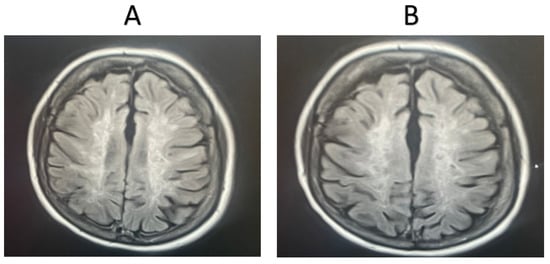

3.2. Magnetic Resonance Imaging Results